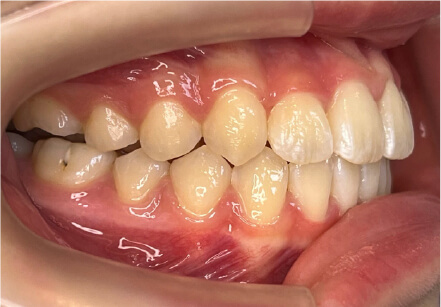

叢生の症例

41歳

/

女性

相談内容

横から見た時のガタガタが気になる

カウンセリング・診断結果

インビザライン、正中は上11に合わせていく、抜歯・拡大装置・IPR・アタッチメントOK

治療内容・方法

アライナー矯正

術後の経過・現在の様子

クリアライナー使用

治療のリスク

痛み・歯根吸収・歯肉退縮・虫歯・後戻り

費用・治療期間

880,000円、7ヶ月

トレーニングなど